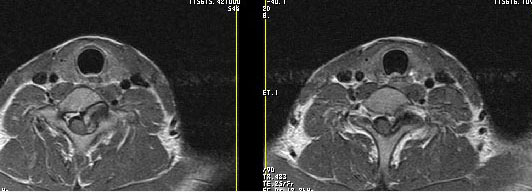

男24岁因一年来感头昏,查体四肢肌力及感觉无异常。颈椎dr未见异常,mri发现c7水平段椎管内左侧占位。患者于7年前有车祸伤病史(但是未检查,自述无异常)。请讨论是否是机化血肿或骨折片,能除外是肿瘤?

强化

椎管内骨性肿块,与第7颈椎左下关节突关系密切,向椎管内生长,第7颈椎椎体左后缘受压变形,边缘可见硬化边,与肿块间间隙清晰。mri扫描肿块内可见骨髓信号,考虑骨软骨瘤可能性大。